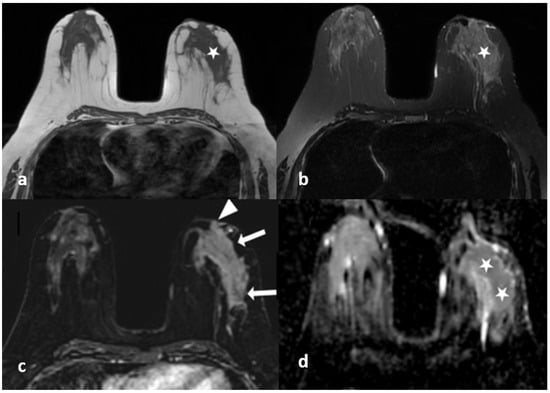

Figure 3.

A 45-year-old woman with histopathologically proven idiopathic granulomatous mastitis involving the right breast. (a) Precontrast T1-weighted fast spin echo axial MR image of the patient shows dilated ducts with a high signal intensity in retroareolar region (arrows). (b) Axial fat-saturated T2-weighted image corresponding to (a), which reveals that the dilated duct has a signal loss in accordance with the fat contained (arrows). (c) Contrast-enhanced subtracted image demonstrates a non-mass enhancement with a clustered ring pattern in the upper outer quadrant of the right breast (arrowhead). (d) T2-weighted fat-saturated image corresponding to (c) also demonstrates the dilated ducts containing fat intensity within the enhanced area (arrow).